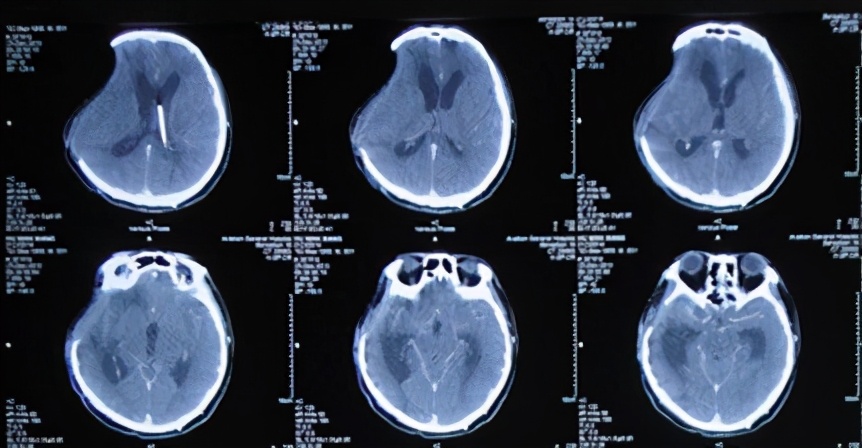

2013年11月21日即抗感染23天后即入院术后第51天(开颅术后第67天),给予试夹闭引流管视察骨窗情况。但在夹毕引流管次日患者出现右侧骨窗膨隆伴嗜睡,复查头CT:脑室系统扩张明显(图-16),再次给予开放脑脊液引流管。

图-16:2013年11月22日头CT

2013年12月17日即继续脑脊液引流25天后即入院术后第77天(开颅术后第93天),进行了侧脑室腹腔分流术,分流术后第1天2013年12月18日术后情况稳定(图-17)。

术后患者恢复良好,但仍间断头痛发作,在2013年12月25日即分流术后第8天(开颅术后第101天),复查头CT:脑室无异常(图-18)。

图-18:2013年12月25日头CT